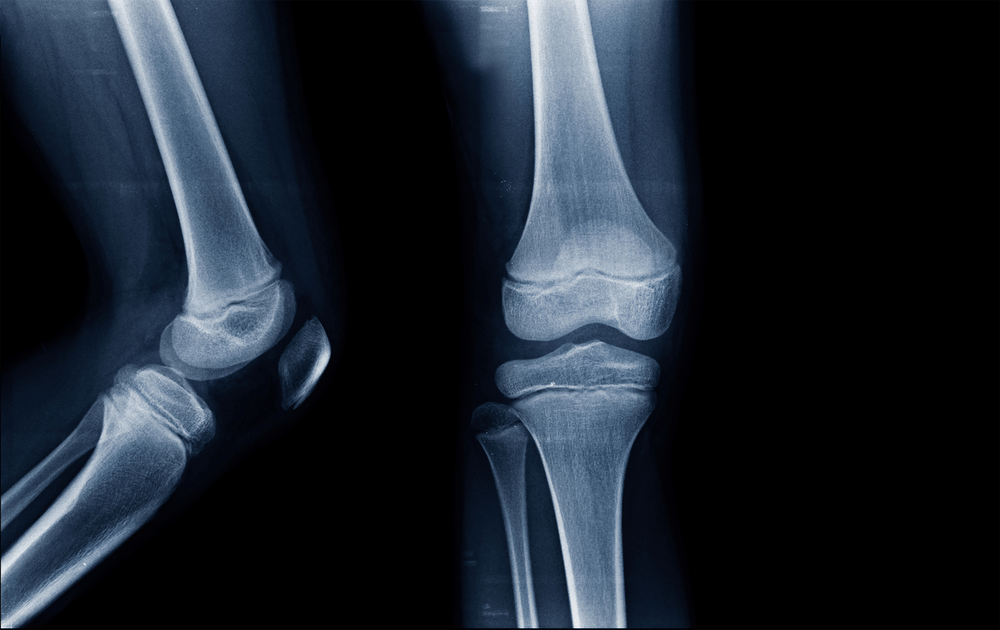

ချော်လဲတာကြောင့်ဖြစ်ဖြစ်၊ မတော်တဆထိခိုက်မိတာတွေကြောင့်ဖြစ်ဖြစ် အရိုးကျိုးတာမျိုးတွေဖြစ်နိုင်ပါတယ်။ အရိုးကျိုးတာက သာမန်မျက်စိနဲ့ မြင်ဖို့ခက်သလို သေချာလေးဂရုစိုက်ပေးဖို့လည်း လိုပါတယ်။ အရိုးပြန်ဆက်တဲ့အချိန်မျာ အစားအသောက်၊ အနေအထိုင်ကို သေချာလေးဂရုစိုက်ပေးမှာ အရိုးက အကောင်းဆုံးပြန်ဆက်နိုင်မှာပါ။ ဒီတော့ အကြောင်းအရင်းတစ်ခုခုကြောင့် အရိုးကျိုးသွားတဲ့အခါ အရိုးမြန်မြန်ဆန်ဆန်ပြန်ဆက်စေဖို့ ဘာတွေလိုက်နာဖို့လိုမလဲဆိုတာကို ဒီဆောင်းပါးလေးကနေ မျှဝေပါရစေ။ ခန္ဓာကိုယ်ရဲ့ ငြမ်းဖြစ်တဲ့အရိုးတွေကို ဘယ်လိုဖွဲ့စည်းထားတာလဲ............ ခန္ဓာကိုယ်ရဲ့ အခြေခံကျတဲ့ ငြမ်းတွေဖြစ်တဲ့ အရိုးတွေကို ကော်လာဂျင်လို့ ခေါ်တဲ့ (ပရိုတင်း) နဲ့ဖွဲ့စည်းထားပြီး အပေါ်ကနေမှ သတ္တုဓာတ်တွေဖြစ်ကြတဲ့ ကယ်လ်ဆီယမ်နဲ့ ဖော့စဖရိတ်တို့က ကြံ့ခိုင်မှုကို အားဖြည့်ပေးထားကြပါတယ်။ ဒါကြောင့် အရိုးတွေကျန်းမာနေစေဖို့ ထိခိုက်သွားတဲ့အခါ အမြန်ဆုံးပြန်ကျန်းမာလာစေဖို့အတွက် အာဟာရတွေကို ပြည့်ဝမျှတအောင်စားသုံးပေးဖို့ လိုပါမယ်။ ကျိုးသွားတဲ့အရိုး မြန်မြန်ပြန်ဆက်စေဖို့ အရိုးတွေကျိုးသွားတဲ့အခါ ပြန်ဆက်ပြီး အမြန်ဆုံးအကောင်းပကတိပြန်ဖြစ်စေဖို့ဆိုရင် ပုံမှန်ထက် အာဟာရဓာတ်တွေကို ပိုမိုစားသုံးပေးဖို့လိုအပ်ပါမယ်။ ဒီတော့ ဘာတွေစားမလဲ......... ကယ်လ်ဆီယမ် အရိုးတွေနဲ့သွားတွေ ကြံ့ခိုင်သန်စွမ်းစေဖို့ မရှိမဖြစ်လိုအပ်မယ့်ဓာတ်တစ်မျိုးပါ။ အရိုးရဲ့ သိပ်သည်းဆကို […]